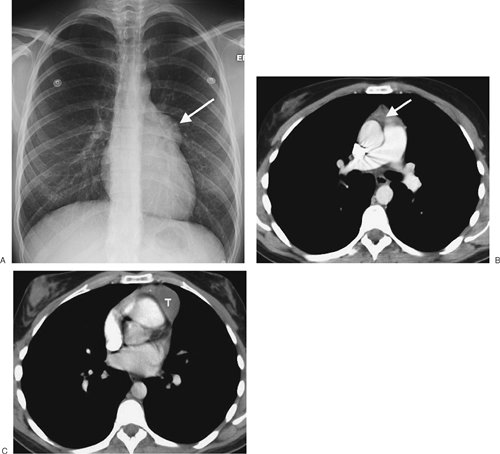

FIGURE 6-10. Benign cystic thymoma. A: PA chest radiograph shows an abnormal left mediastinal contour (arrow). B: Lateral view shows a round, circumscribed mass with a high-attenuation rim in the anterior mediastinum (arrows). C: CT scan shows a mass of soft tissue attenuation (T) with dense rim calcification anterior to the ascending aorta.